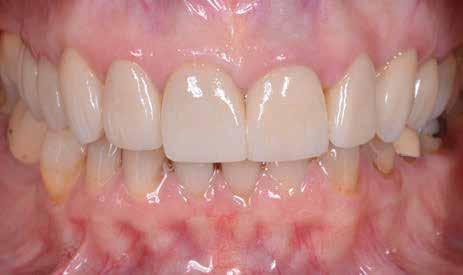

Az oxigén inhibíciós réteg kialakulásának elkerülése érdekében a kerámiafelszíneket glicerin géllel (Liquid Strip, Ivoclar Vivadent, Schaan, Liechtenstein) borítottuk, majd ezeket a felszíneket ismét 20-20 másodpercen keresztül világítottuk. A végeredmény megfelelt a páciens esztétikai igényeinek (6. a. ábra). Az átadott restaurátumok épségének megőrzése érdekében, a páciens számára éjszakai fogvédő sín készült. Az ötéves kontroll alkalmával megállapítottuk, hogy az elvégzett kezelésünk továbbra is sikeresnek tekinthető (6. b. ábra)

Az általunk alkalmazott adhezív rendszerek hatékonyságát nagymértékben növelhetjük azáltal, hogy a fogakat minimál invazív módon, azaz csak zománcon belül preparáljuk, és a kerámia héjakat kofferdám izolálásban ragasztjuk. Jelen esetismertetésünknek az volt a célja, hogy bemutassuk, hogyan lehet az adekvát módon kivitelezett kofferdám izolálással megelőzni

a munkaterület nyállal, vérrel vagy szulkusz-váladékkal történő kontaminációját. A megfelelő méretben kialakított perforációs nyílások és köztük lévő optimális távolság elengedhetetlen ahhoz, hogy a kofferdámot ideális módon tudjuk felhelyezni. Ezzel az esettel azt is bizonyítjuk, hogy a gumilepedő levegőfújással, fogselyemmel és teflonszalagok segítségével történő beforgatásával az ínyvérzés kialakulását el lehet kerülni. Ismételten szeretnénk hangsúlyozni, hogy a megfelelő kofferdám kapcsok használata nélkül nem tudtuk volna a preparált csonkszélt a gumilepedő szélétől eltartani. A kezelés során elért eredményeket jól alátámasztotta, hogy a páciens az ötéves kontroll vizsgálat során teljesen elégedett volt.

A páciens elégedett volt a végleges restaurátumok színével, formájával és méretével. A kezelés végeredménye kielégítette az esztétikai elvárásait (9. ábra). A frissen átadott restaurátumok épségének megőrzése érdekében a páciens számára éjszakai fogvédősínt készítettünk. A páciensünk a négyéves kontrollvizsgálat során is nagyon elégedett volt a kezelés eredményével. A korábban meglévő fekete háromszögek eltűnésének különösképpen örült (9. és 10. ábrák)

9. ábra. A beavatkozás után, valamint a 4 évvel később látható állapot. (A): Egy héttel a ragasztás után készült felvétel. (B): A négyéves kontroll alkalmával készült felvétel.